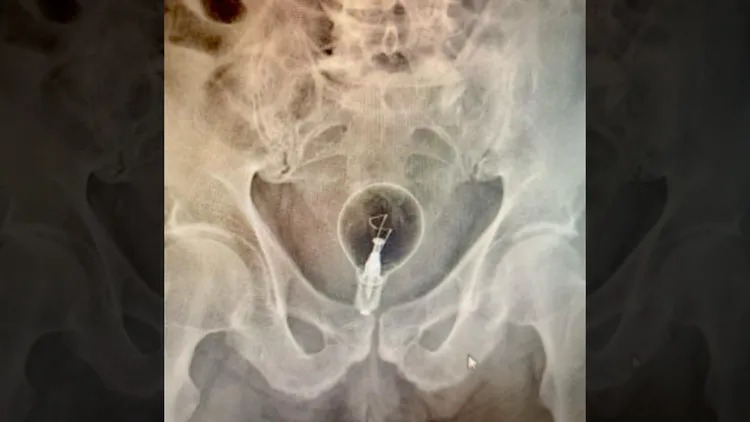

醫護人員到場後,才知道老翁竟是將燈泡塞入體內,隨即將人緊急送醫救治。醫師檢查後,驚見X光竟有一顆完整的燈泡,事後用手術鉗才成功將燈泡取出,並安排住院治療觀察情況。對此,雖老翁未說明為何離奇將燈泡塞入體內,但醫師研判是「色情實驗」。